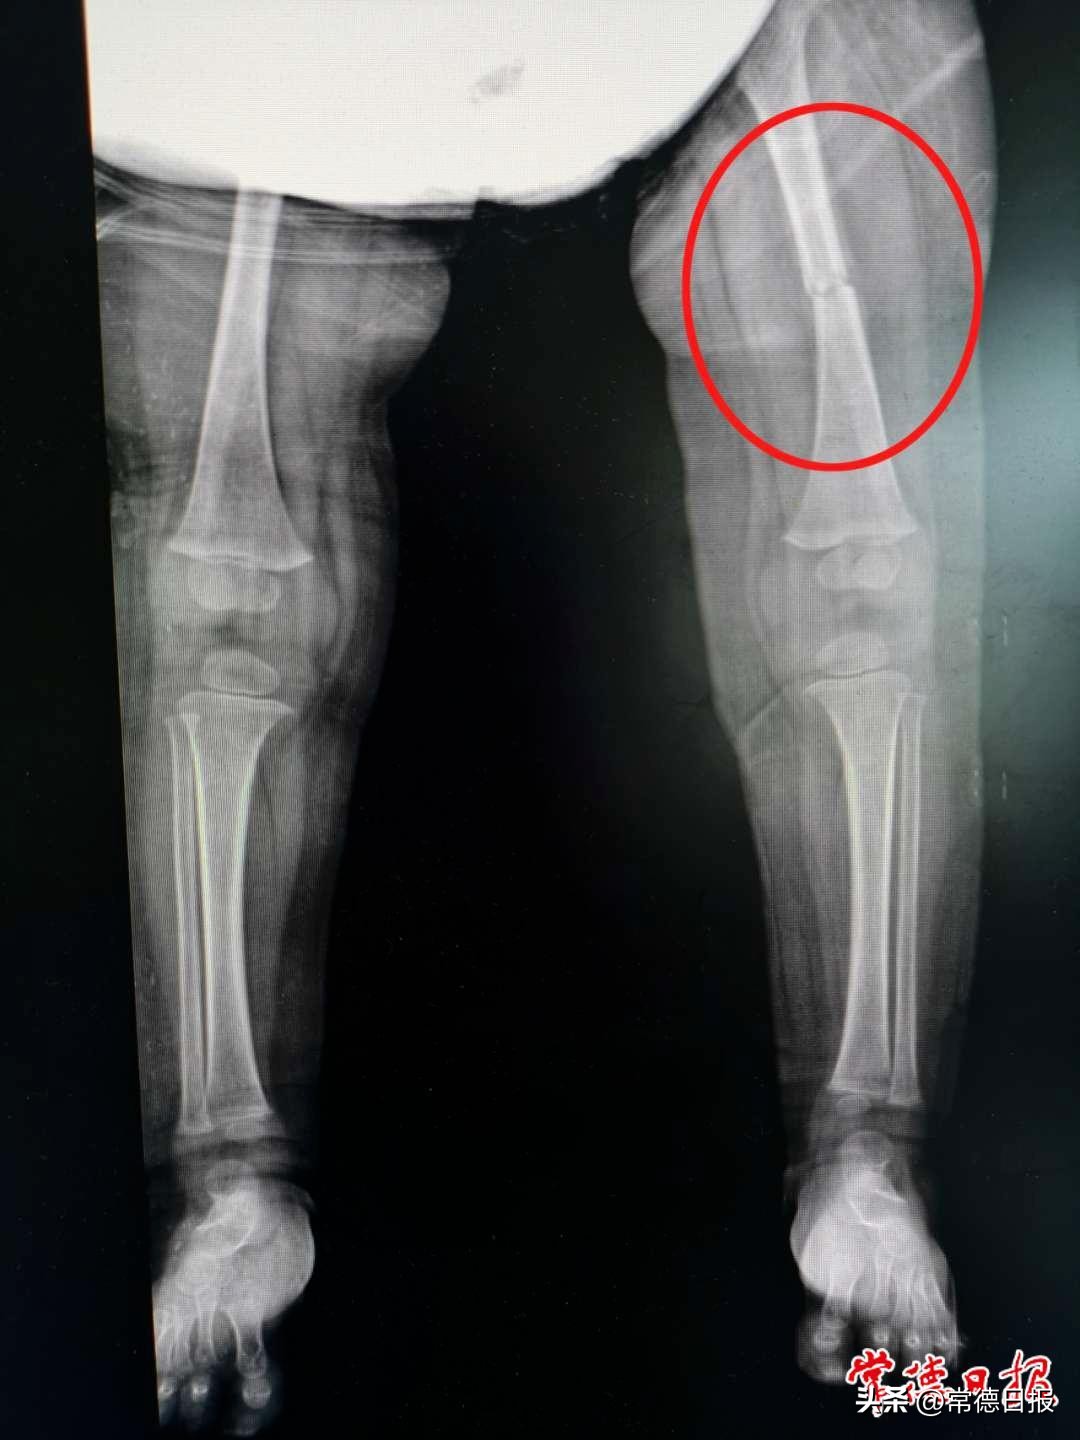

影像学显示田田的左侧股骨干骨折

医院骨伤三科(手足、小儿病区)主治医师田忠接诊了田田并为其完善了各项相关检查,最终以“左侧股骨干骨折”收治入院,并通过仔细地查体及阅片讨论,决定为田田予以双下肢悬吊牵引制动治疗。